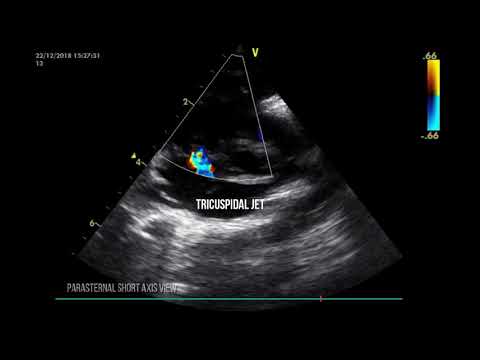

Pulmonary Hypertension in the NICU